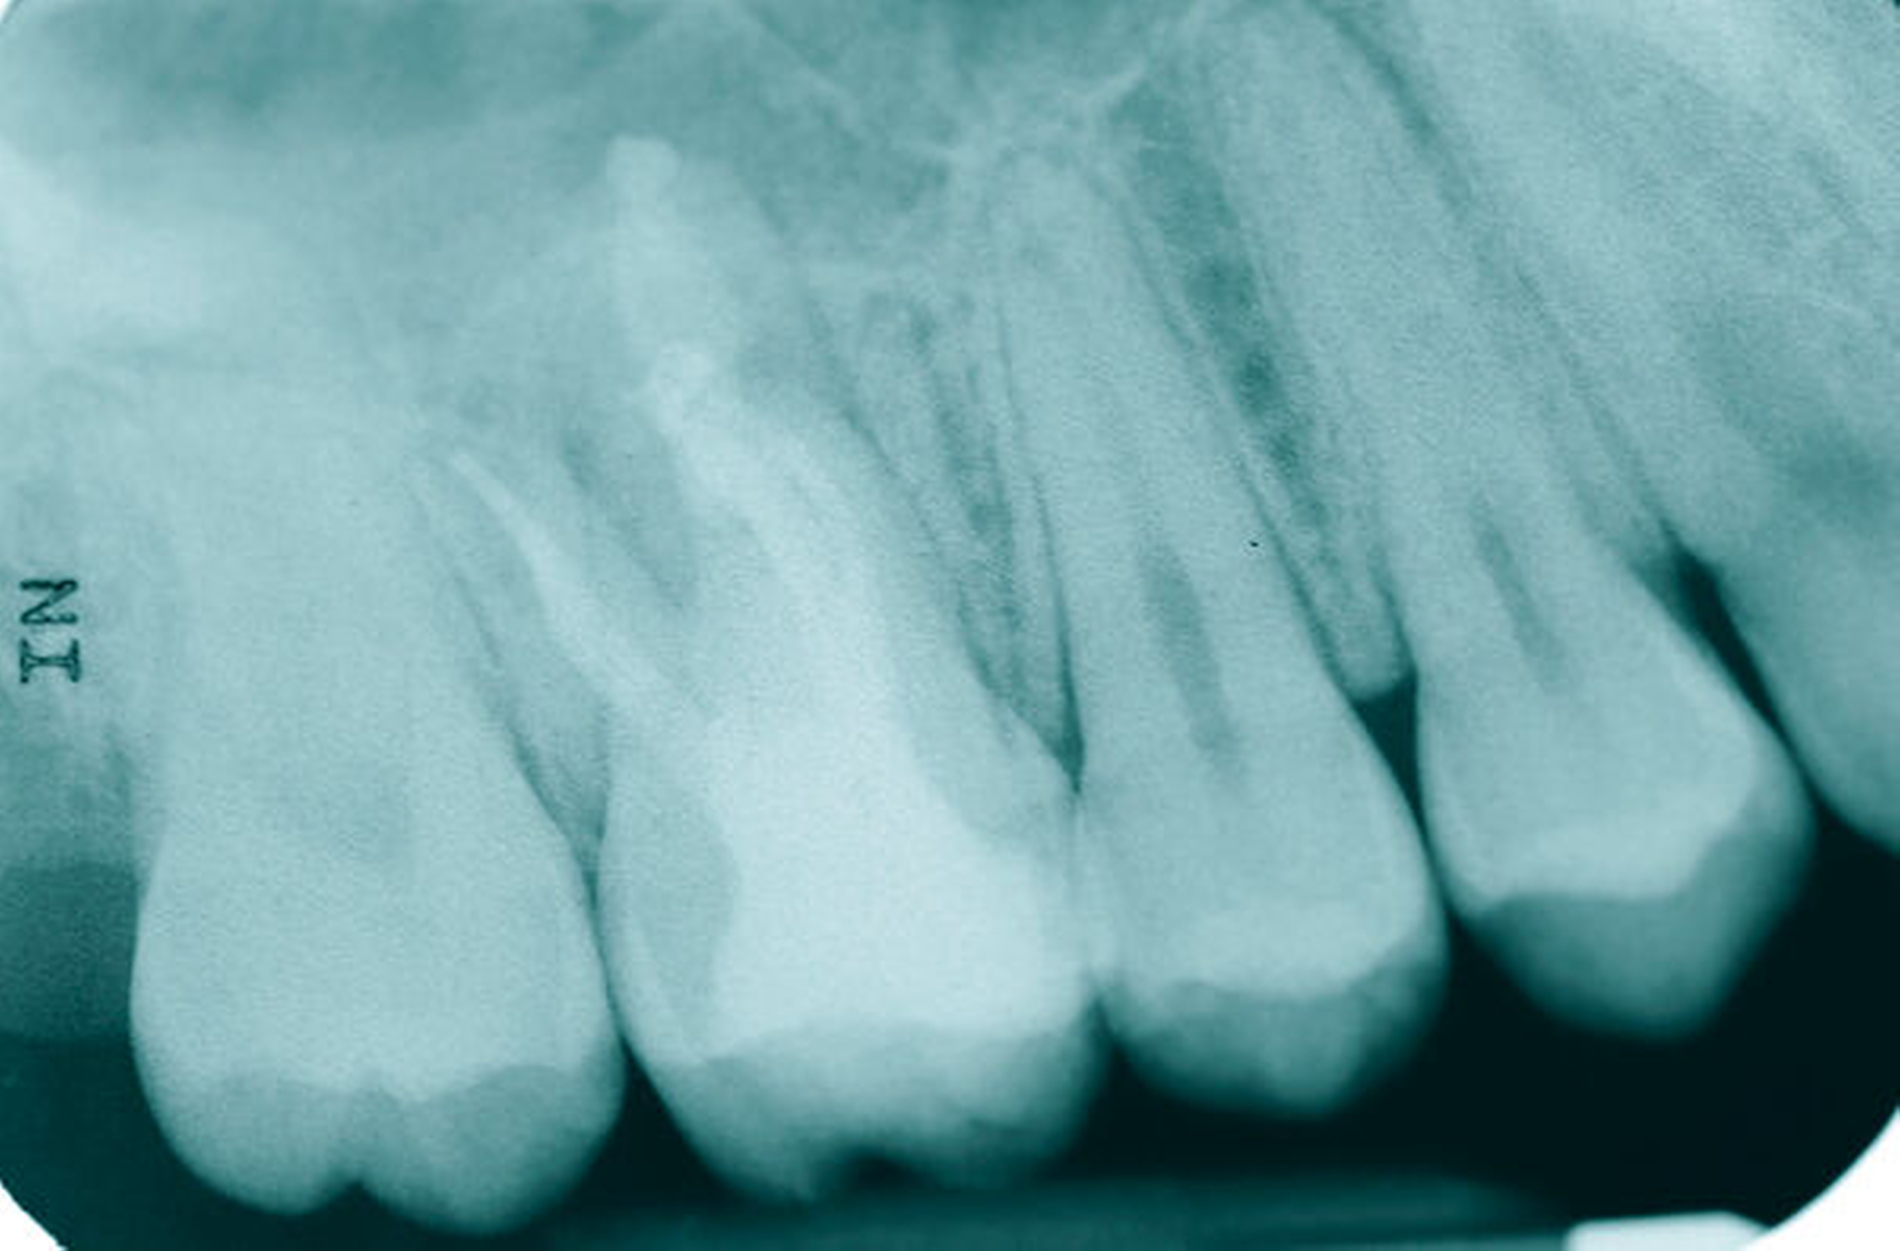

Eine 53-jährige Patientin stellte sich 2015 mit plötzlich aufgetretenen, starken Beschwerden an Zahn 16 und der Bitte um Abklärung vor. Es erfolgte die klinische und röntgenologische Befundung des Zahnes, der neben einer apikalen Parodontitis auch eine große, fast bis in die Furkation reichende Kronenrandkaries an der mesiobukkalen Wurzel aufwies. Um diesen vorhersagbar versorgen zu können, wurde der Patientin die endodontische Behandlung mit Amputation der mesiobukkalen Wurzel und anschließender Versorgung mittels Vollkrone als Alternative zur Extraktion aufgezeigt. Sie entschied sich für den Zahnerhalt.

So folgte nach der Wurzelfüllung die Amputation der mesiobukkalen Wurzel. Der Zahn wurde nach der Amputation auf Wunsch der Patientin zunächst mit einem Langzeitprovisorium versorgt, das im Verlauf gegen eine definitive Versorgung ausgewechselt wurde. Die Patientin ist seitdem an 16 beschwerdefrei, der Zahn ist stabil und hat eine gute Langzeitprognose.